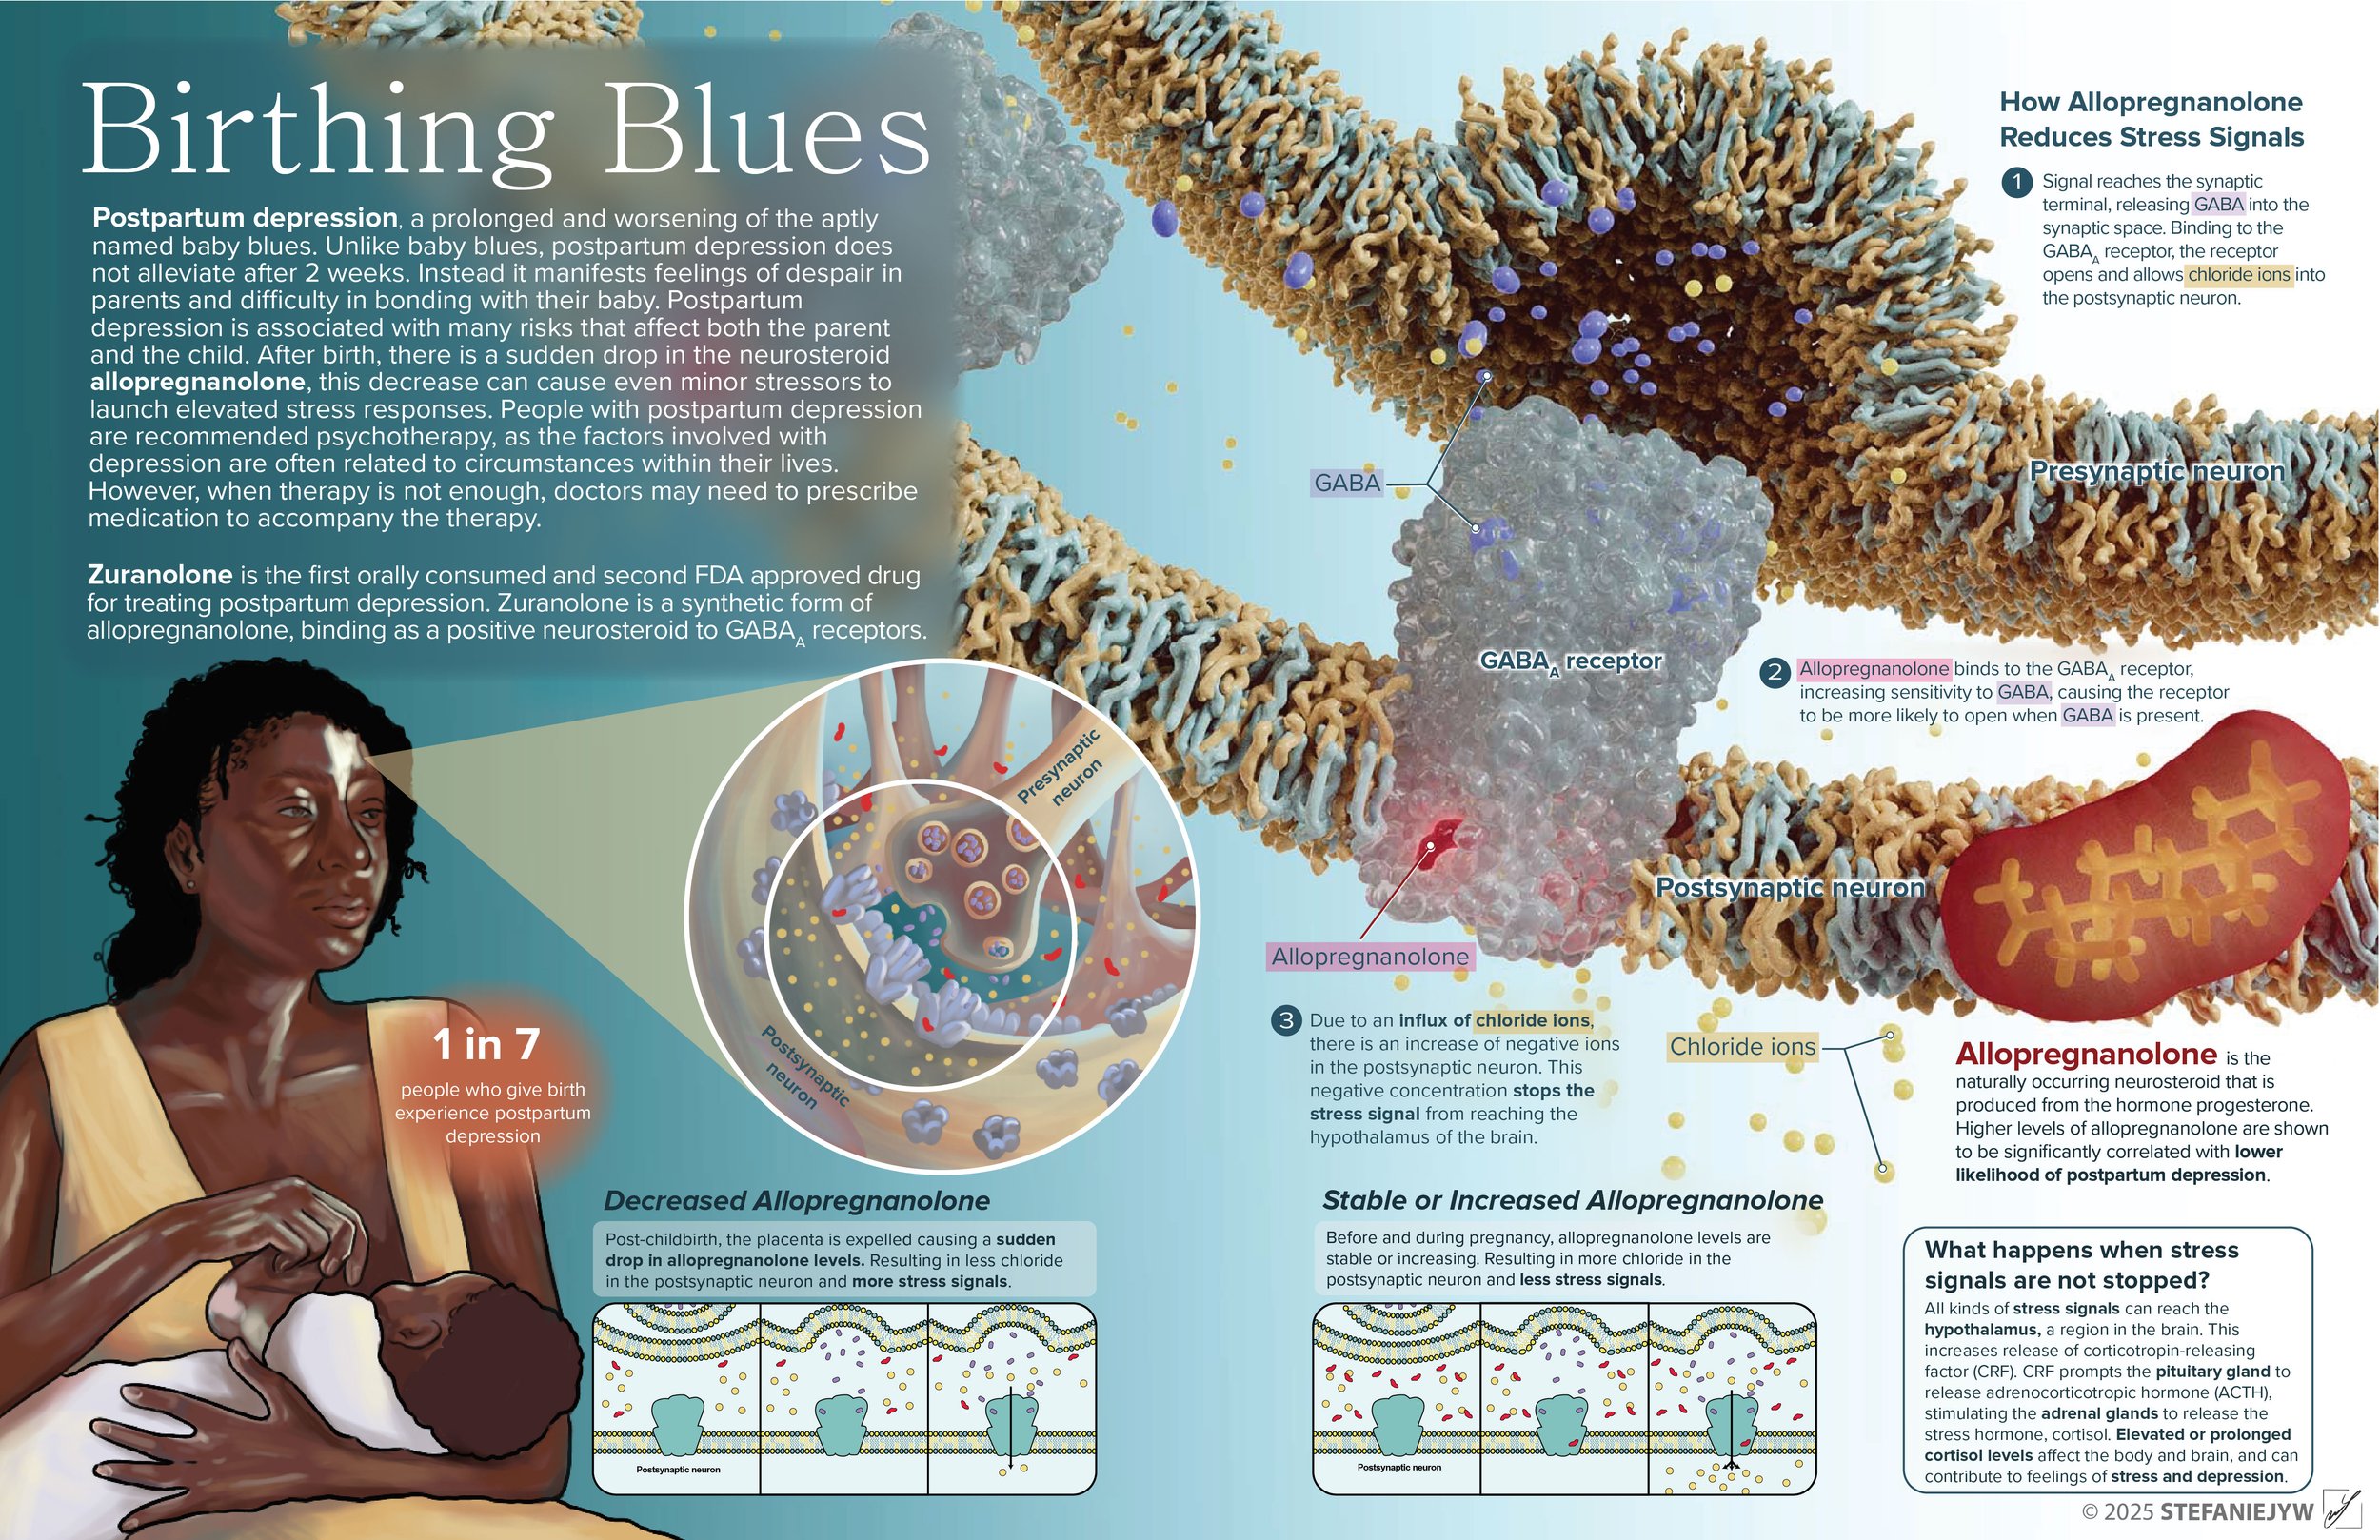

Craniosynostosis Care

Explore a curated collection of our past work, where imagination meets strategy. Each project reflects our drive to deliver thoughtful, effective solutions.

Series: Inclusive Anatomy